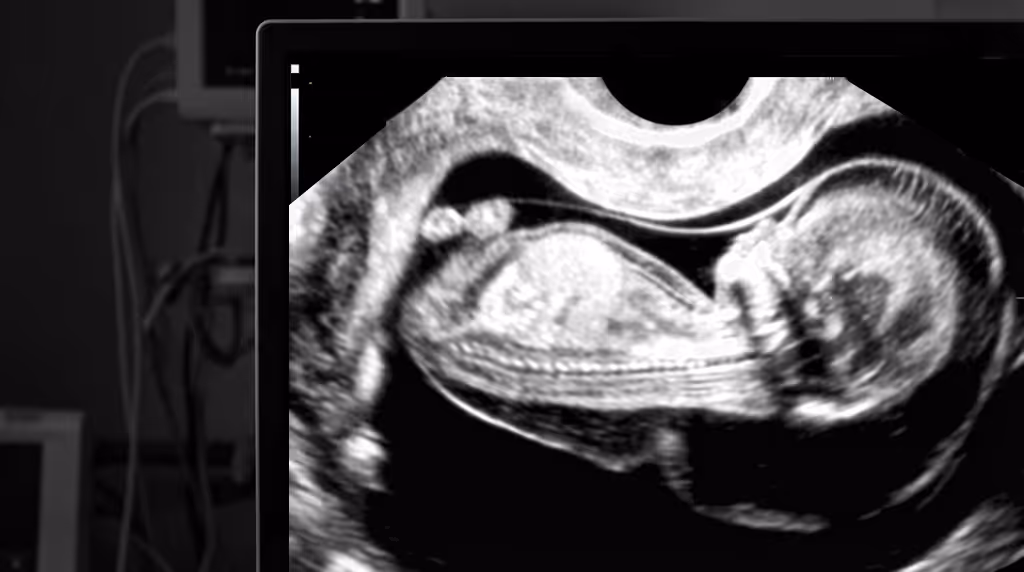

Every practitioner performing early pregnancy scans has encountered a 10-week fetus with a “hydropic appearance” or marked skin oedema. In such situations, professionals often feel frustrated: the baby looks unwell, yet there is no clear pathway for management. The immediate questions are whether to inform the parents and which tests to arrange, or where to refer. It is clear that the CVS option does not exist at 10 weeks. So, should we “ignore” the finding and rescan in two weeks to measure the NT? Does that sound correct?

We have developed a clear, streamlined 10 weeks NT pathway that combines high-resolution scans with advanced NIPT. Train with us, partner with us, and improve care for pregnant women.

If you have a patient at 9–10 weeks with increased nuchal translucency (NT), generalised fetal oedema, cystic hygroma, or early fetal hydrops, please refer her to our clinic for assessment and discussion of the SMART NT pathway. She will receive a discounted 10-week scan as soon as possible (usually within 24–48 hours), discounted KNOVA NIPT, and a targeted scan at 12–13 weeks.

This pathway may be less practical because of the logistics of travelling to London. We will accept a report from an NHS or other CQC-registered ultrasound provider (an image of the increased NT measurement is essential). We will arrange online NIPT counselling promptly and send a KNOVA kit by courier with instructions. We strongly advise arranging and attending our clinic for the 12–13-week targeted scan.

NT scan and NIPT at 10 weeks; full results by 12 weeks